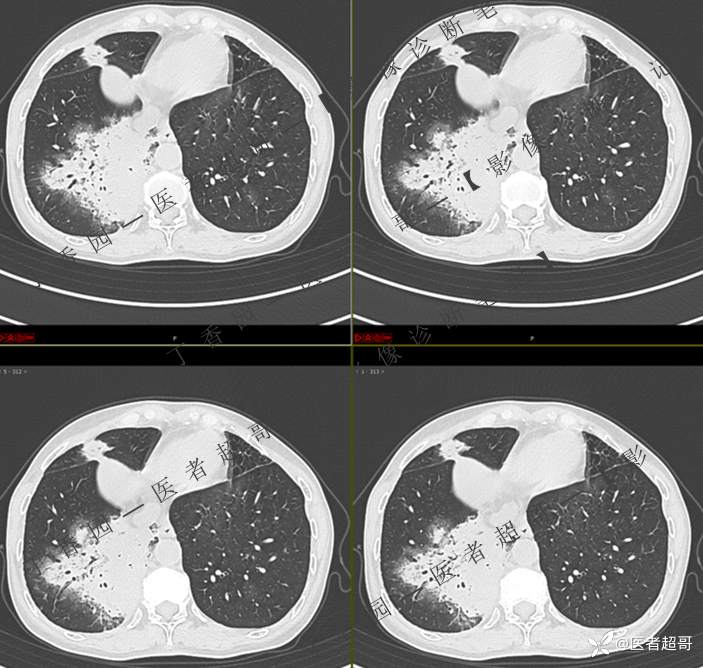

临床治疗一周后复查